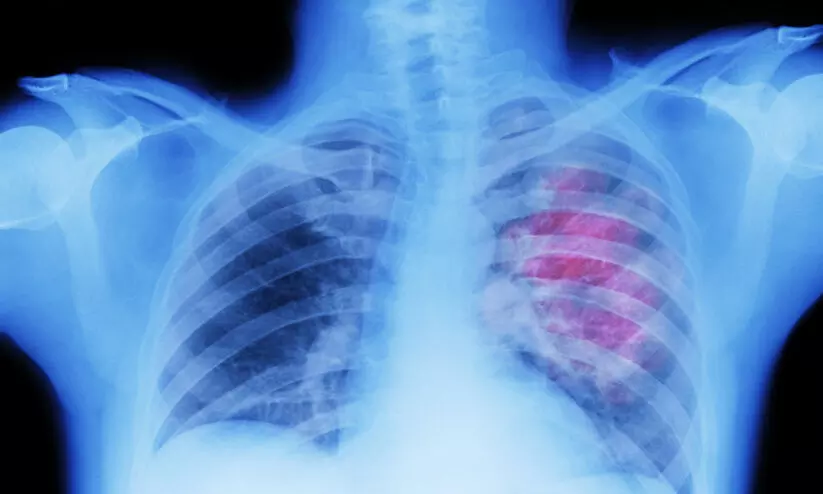

പുകവലിക്കാത്തവരിലും ശ്വാസകോശ കാൻസർ വർധിക്കുന്നു

text_fieldsന്യൂഡൽഹി: കാൻസറുമായി ബന്ധപ്പെട്ട മരണങ്ങളിൽ പ്രധാനമാണ് ശ്വാസകോശത്തെ ബാധിക്കുന്നത്. പുകവലിയും വായു മലിനീകരണവുമാണ് ശ്വാസകോശ അർബുദത്തിന് പ്രധാനമായും കാരണമാകുന്നത്. അതേസമയം, പുകവലിക്കാത്തവരിലും ശ്വാസകോശ കാൻസർ വർധിക്കുകയാണെന്ന് പുതിയ പഠനം.

53 മുതൽ 70 ശതമാനം ശ്വാസകോശ കാൻസറും ഒരിക്കലും പുകവലിക്കാത്തവരിലാണ് കണ്ടെത്തിയിട്ടുള്ളതെന്നാണ് പഠനം പറയുന്നത്. ലോക കാൻസർ ദിനമായ ഇന്ന് ദി ലാൻസെറ്റ് റെസ്പിറേറ്ററി മെഡിസിൻ ജേണലിലാണ് പഠനം പ്രസിദ്ധീകരിച്ചത്.